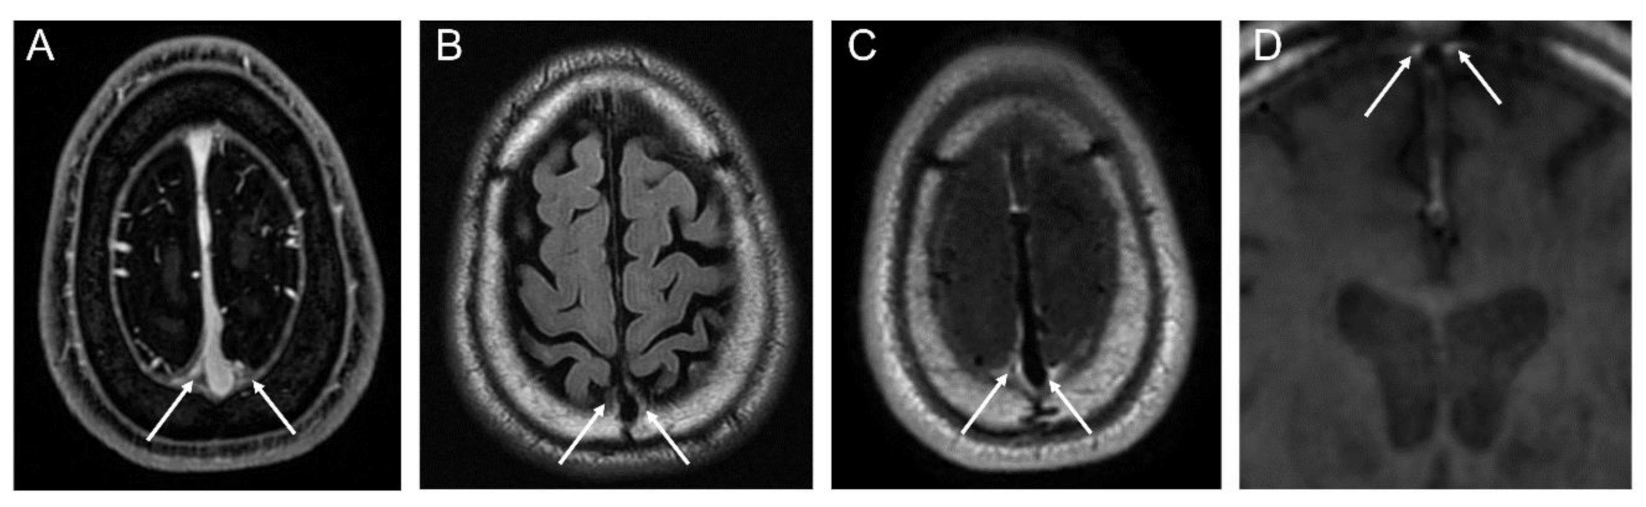

We identified the peri-sinus lymphatic space (Figure 2) as the enhancing structure located next to the superior sagittal sinus visible on coronal contrast-enhanced 3D T1-weighted black-blood images with high signal intensity on FLAIRs, as suggested by the previous literature [8,15]. The volume of dura-associated lymphatics (Figure 3) was measured from the mid-portion at the eyeball level through to the torcular herophili level by a region of interest (ROI) drawn section-by-section on coronal contrast-enhanced 3D T1-weighted black-blood images using a semiautomatic method with an interactive level-set volume of interest. Threshold-based algorithms were employed using ITK-SNAP and 3D slicer (version 4.9.0; available at: http://slicer.org/software). The ROI was drawn by a neuroradiologist (M.P.) with 7 years of experience who was blinded to all corresponding clinical information. Another neuroradiologist (S.J.A.) with 9 years of experience) drew ROIs in 15 randomly selected patients for the assessment of interrater reliability. The peri-sinus lymphatic volume was normalized with ICV using the residual method, which is known to be less susceptible to systematic and random errors [16].

Figure 2.

MRI visualization of peri-sinus lymphatic space on conventional contrast-enhanced axial T1-weighted image (A), axial FLAIR image (B), contrast-enhanced axial T1-weighted black-blood image (C), and coronal T1-weighted black-blood image (D).